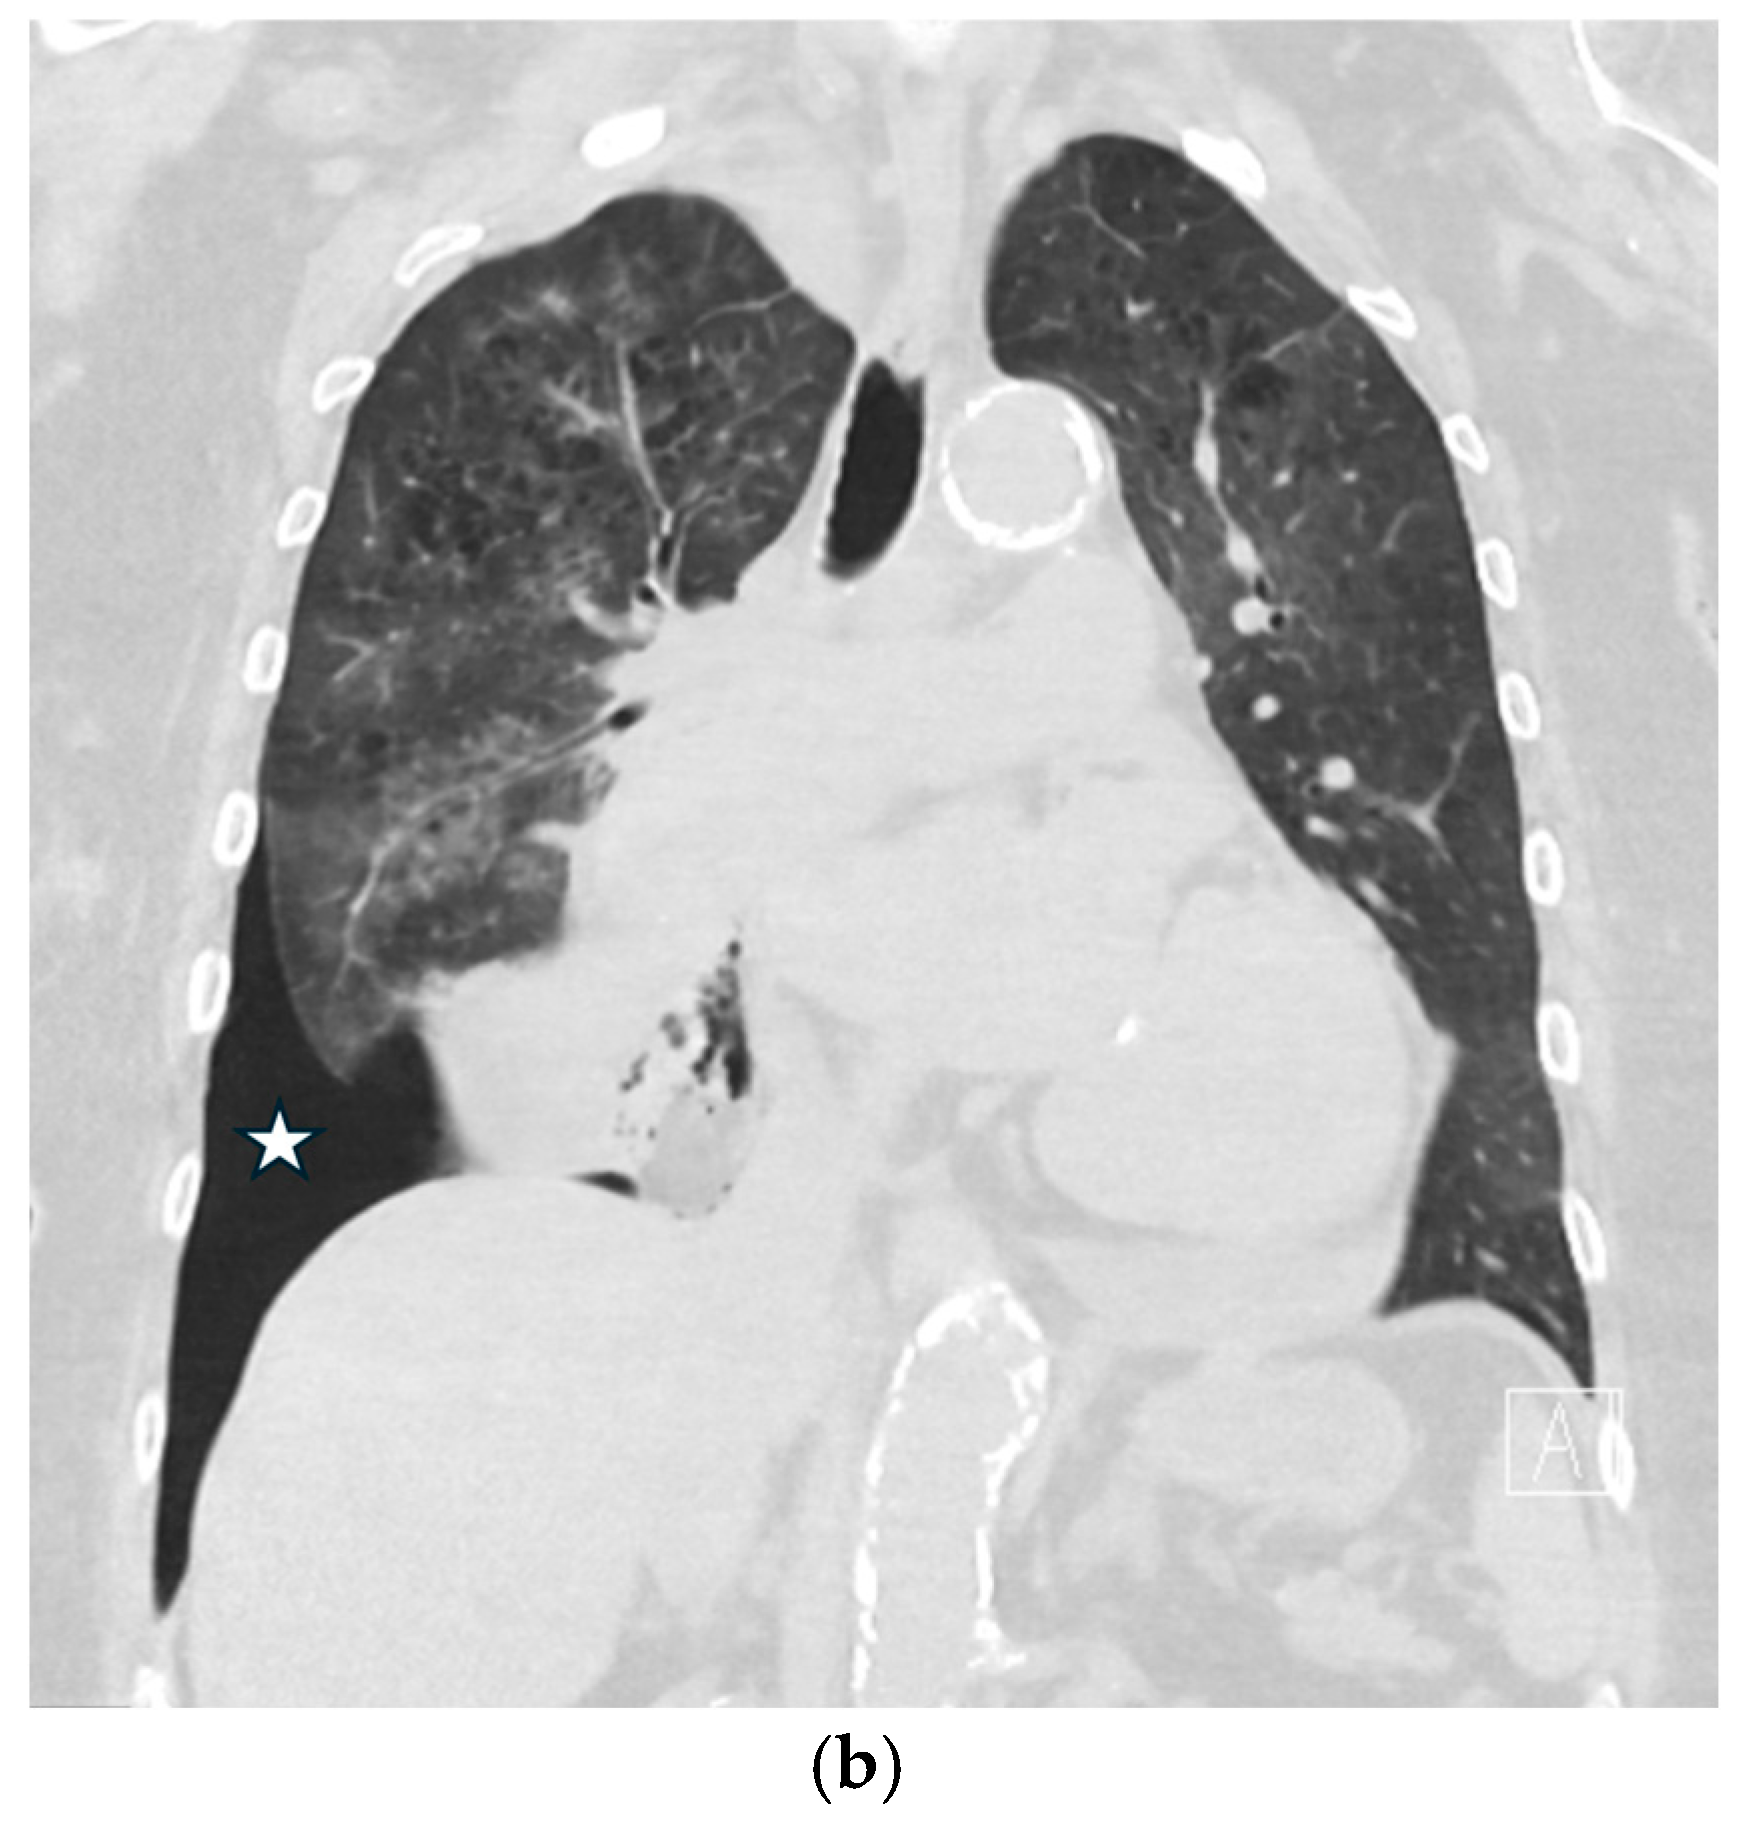

5.1.2. COVID-19 Pneumonia

5.1.3. Pneumocystis jirovecii Pneumonia (PJP)